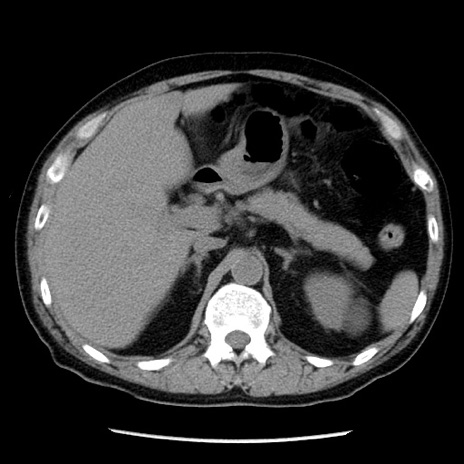

症例29(横断像)

【症例】40歳代男性

【現病歴】2日前から胃痛あり。徐々に周期的な激痛に変化した。本日になっても激痛があるため受診。

【身体所見】意識清明、BT 38-39℃台あり、腹部:膨満、やや硬、右下腹部に圧痛あり。

【データ】WBC 8500、CRP 23.26